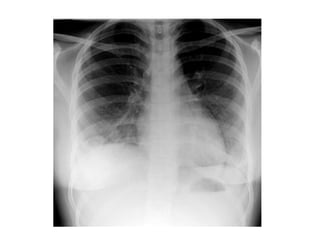

Post infectious pneumatocele, the initial chest x-ray shows

consolidation in the right lung, follow up chest done, when the

patient was asymptomatic, shows multiple thin walled lucencies in

the right lung